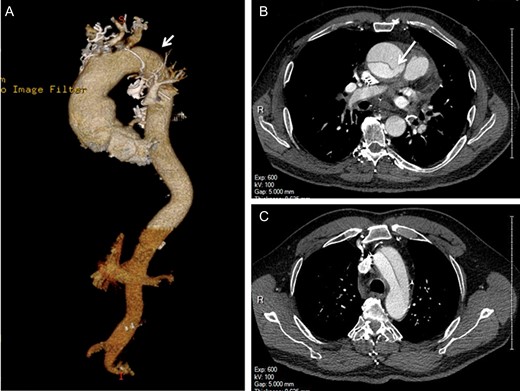

A 79-year-old man with multiple comorbidities presented with acute chest pain, and a computed tomography angiogram (CTA) showed ATAAD extending from the sinotubular junction to the proximal descending thoracic aorta with an intimal tear identified in the ascending but not distal aorta (Fig. 1). The aortic arch was not aneurysmal.

Preoperative computed tomography angiography shows the type A aortic dissection with intimal flap extending from the sinotubular junction to the proximal descending thoracic aorta (A, arrowhead). The primary entry tear is located in the ascending aorta (B, arrow). The re-entry intimal tear is not identified (C).